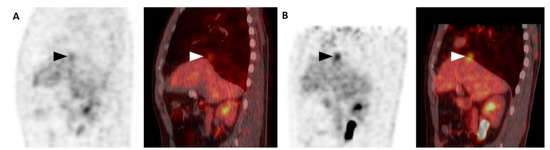

3. Results

4. Discussion